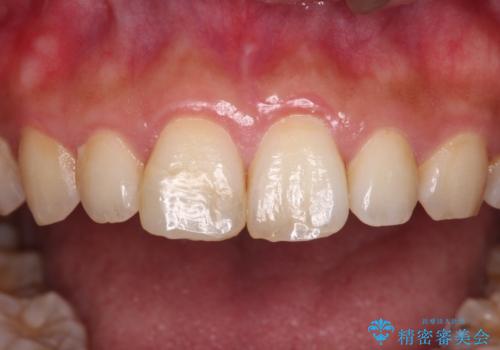

転んで欠けてしまった前歯 オーダーメイドのオールセラミッククラウン

- 転んで欠けてしまった前歯を気にして来院された患者様です。

転んだ際に歯の先端1/4ほどが欠けてしまい、近医にて修復をしてもらったとのことですが、将来的にオールセラミッククラウンを装着する可能性を説明されたため、当院にて補綴治療を行うこととしました。

オーダーメイドタイプのセラミッククラウンは、既製タイプのク色のラウン(スタンダードタイプ)とは異なり、色合いが合うまで何度も修正を行って調整をいたします。